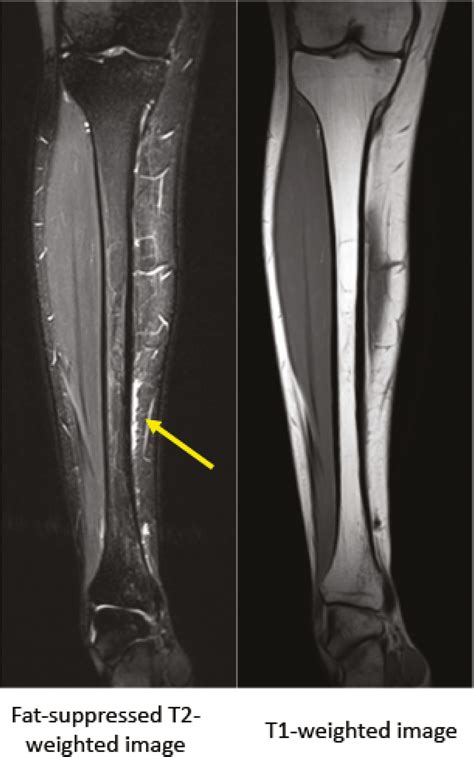

It is important to note that a Shin Splints Xray may not always show abnormalities in the early stages of shin splints, as the condition primarily affects the soft tissues rather than the bone itself. In such cases, additional imaging studies like MRI or ultrasound may be recommended to get a more detailed view of the soft tissues.

• MRI: To assess soft tissue damage and inflammation